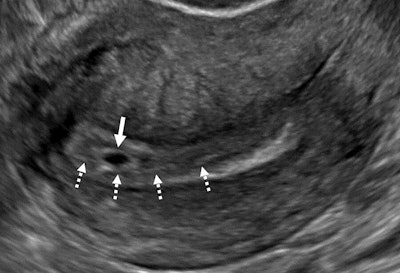

An intradecidual sign depicts transvaginal sagittal grayscale ultrasound imaging in a 34-year-old pregnant patient, which shows a 4-mm empty gestational sac (solid arrow) in the anterior endometrium. The location of the sac to one side of the central hyperechoic line (dotted arrows) representing the opposed innermost layers of decidualized endometrium confirms it is within the endometrium and not the endometrial cavity, hence the name intradecidual sign. This sign is helpful when seen to diagnose a probable intrauterine pregnancy before visualization of the yolk sac. Three days later, the yolk sac was visualized (not shown), allowing for the diagnosis of a definite intrauterine pregnancy.RSNA